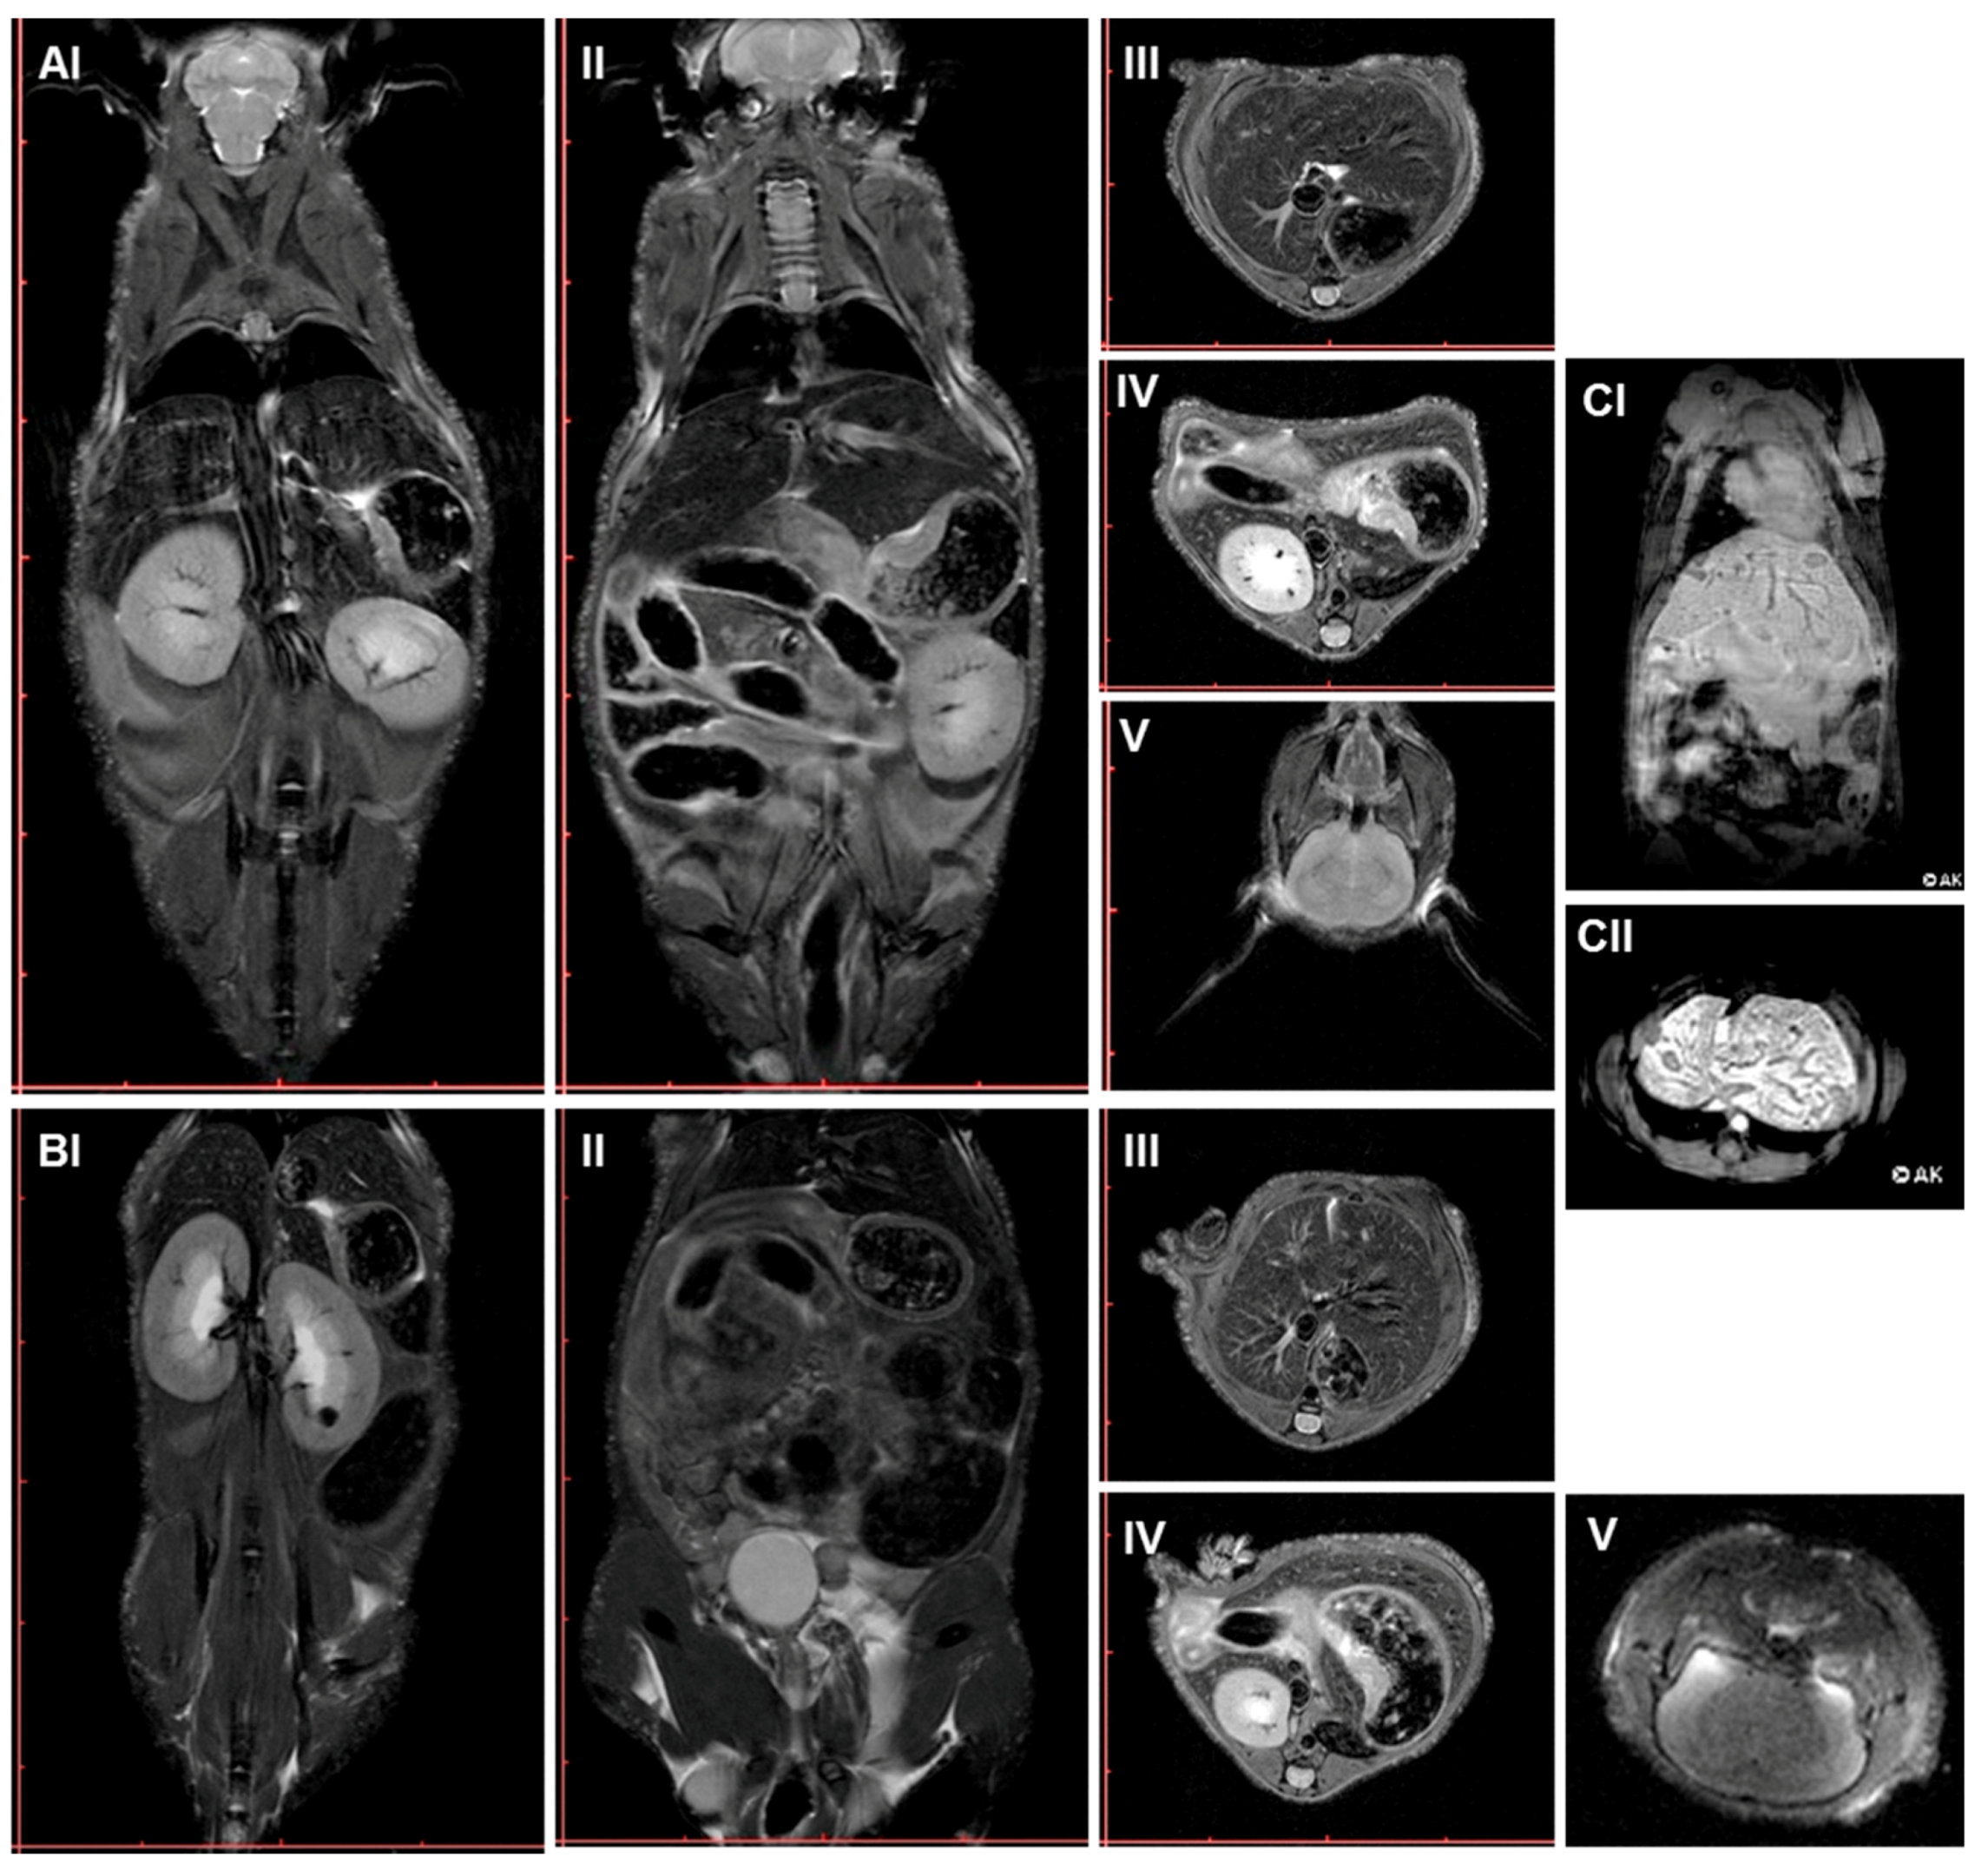

2.3. Multimodal Imaging of Mice 350 Days after Plasma Treatment

4.6. MRI, PET/CT Scans, and Interpretation of Data